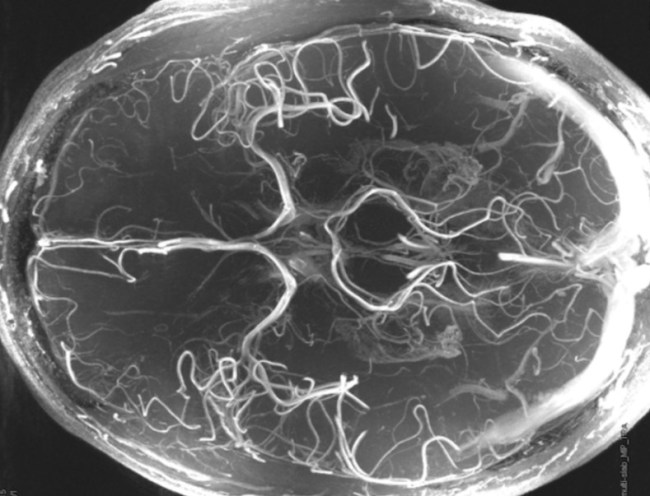

That’s not a picture of his brain, by the way, that’s my brain. It’s just a dope image of my brain I thought you dudes would enjoy. Now let’s move on.